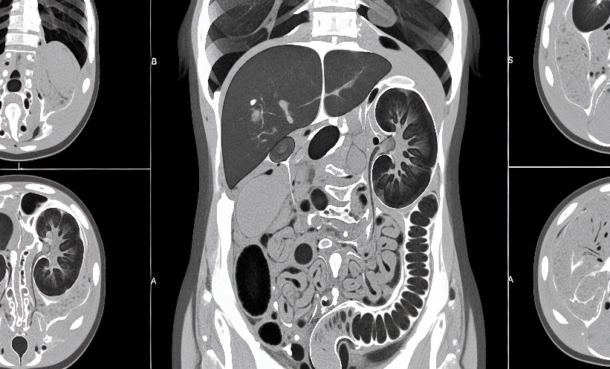

Radiology